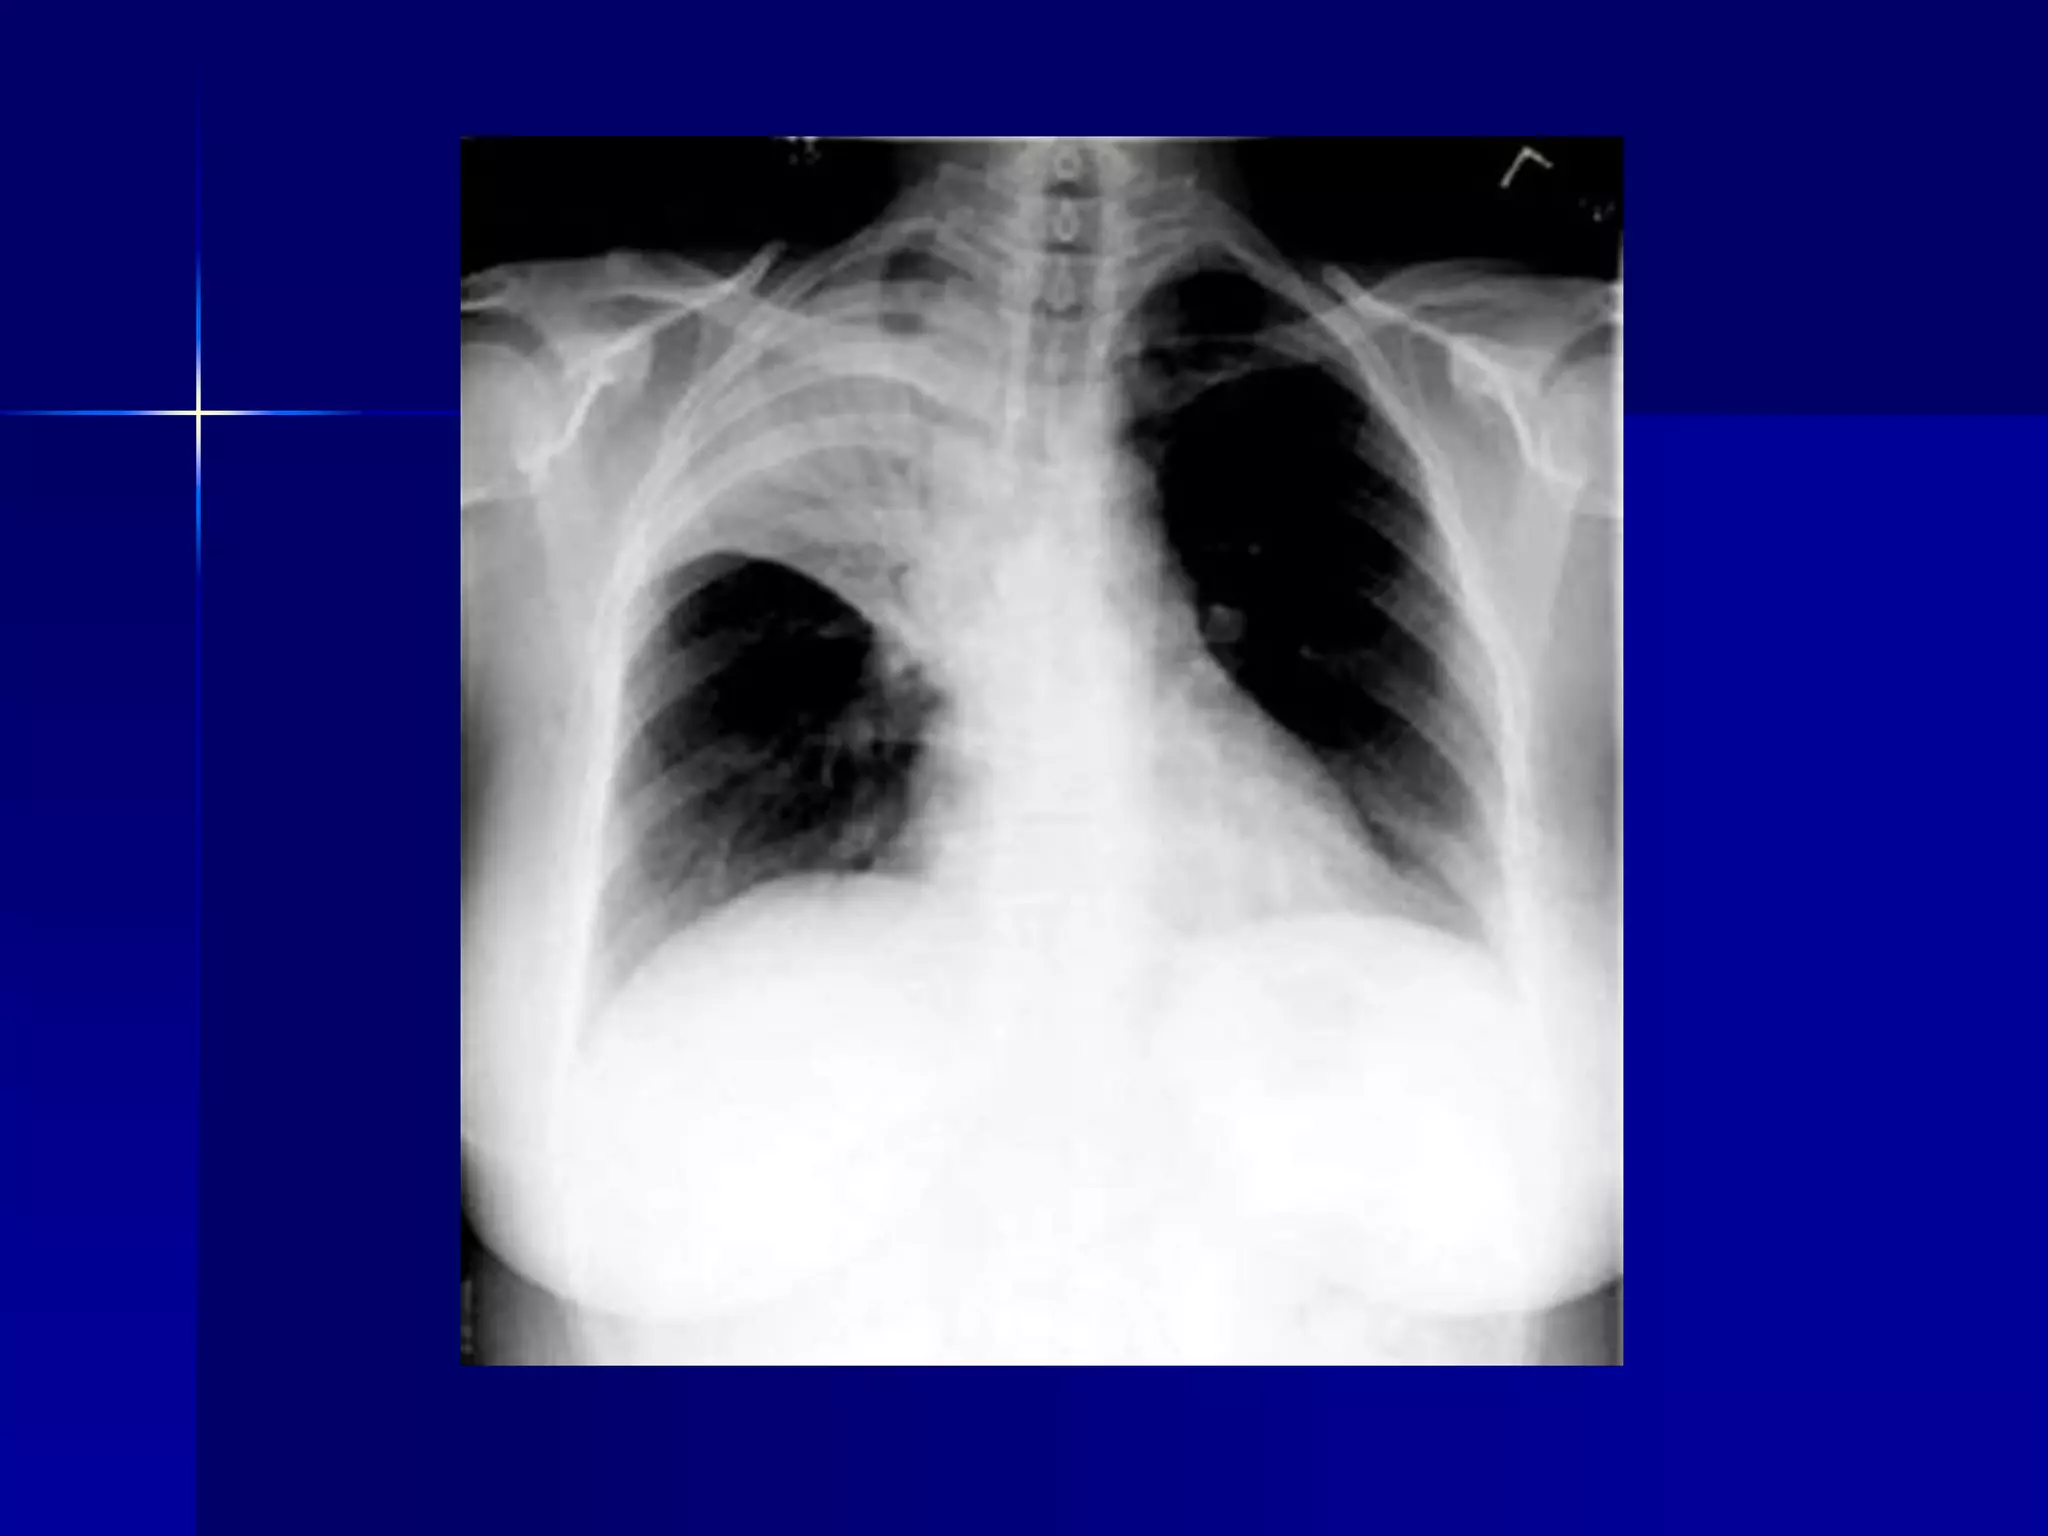

Atelectasis Left Lung

 Homogenous density left hemithorax

 Mediastinal shift to the left

 Diaphragmatic and heart silhouette

are not identifiable